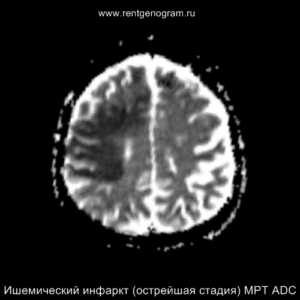

Острая фаза (первые 6 часов)

На МРТ и КТ изменения могут отсутствовать. На МРТ у некоторых пациентов могут быть первые признаки ишемии. На DWI область ишемического повреждения может быть видна через 2,5 часа после появления первых симптомов.

С 4-5 часов на DWI должны быть заметны признаки ишемического поражения, которые представляют собой «ядро» инфаркта.

Диагностика ишемического инсульта: КТ и МРТ

На остром этапе (Т2, Т1 и Flair могут сохранять нормальные результаты), на МРА можно обнаружить окклюзию артерии (при атеротромбоэмболическом и кардиоэмболическом механизмах), что будет выглядеть как отсутствие МР-сигнала от ведущей артерии (ВСА или СМА). Контрастное усиление на МРТ в остром этапе не приводит к накоплению контраста в области повреждения.

Острая фаза (6 — 24 часа)

В течение острого этапа на МРТ и КТ выявляются все морфологические признаки ишемического инсульта. Область острого ишемического инфаркта визуализируется как зона ↑Т2, ↑Flair, ↑DWI и ↓Т1 ↓ADC. Можно обнаружить тромб в артерии. На КТ в остром этапе также чётко дифференцируется поражённая область, представляющая собой участок с потерей дифференциации мозговых структур и снижением их плотности. Контрастирование в остром периоде не показывает патологических участков с накоплением контраста.

Когда в мозговых артериях происходит реканализация кровотока, это может привести к образованию геморрагических пропитываний и кровоизлияний («красный компонент» ишемического инфаркта), что будет отображаться на МРТ как ↑ на Т1 и Т2*, а на КТ — как участки с гетерогенной повышенной плотностью. На более поздних этапах подострой стадии наблюдается нормализация ранее повышенных показателей DWI и ADC, известная как «псевдонормализация» диффузии.